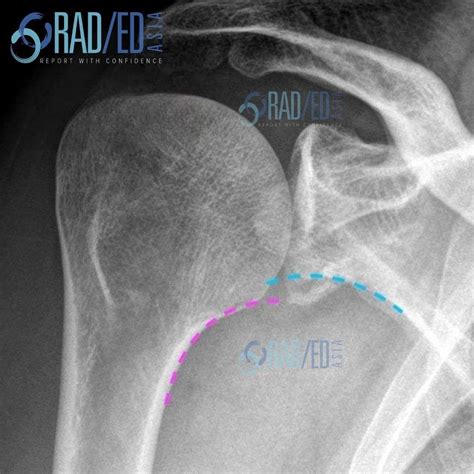

Diagnosis of Inferior Shoulder Dislocation

Diagnosing an inferior shoulder dislocation involves a combination of physical examination and imaging tests. The diagnostic process typically includes:

• Physical examination: A healthcare provider will assess the shoulder for deformity, swelling, and range of motion.

• X-rays: Imaging tests can confirm the dislocation and rule out fractures or other injuries.

• CT scan or MRI: These advanced imaging techniques may be used to evaluate the extent of the injury and plan treatment.

Accurate diagnosis is crucial for determining the appropriate course of treatment and ensuring a successful recovery.